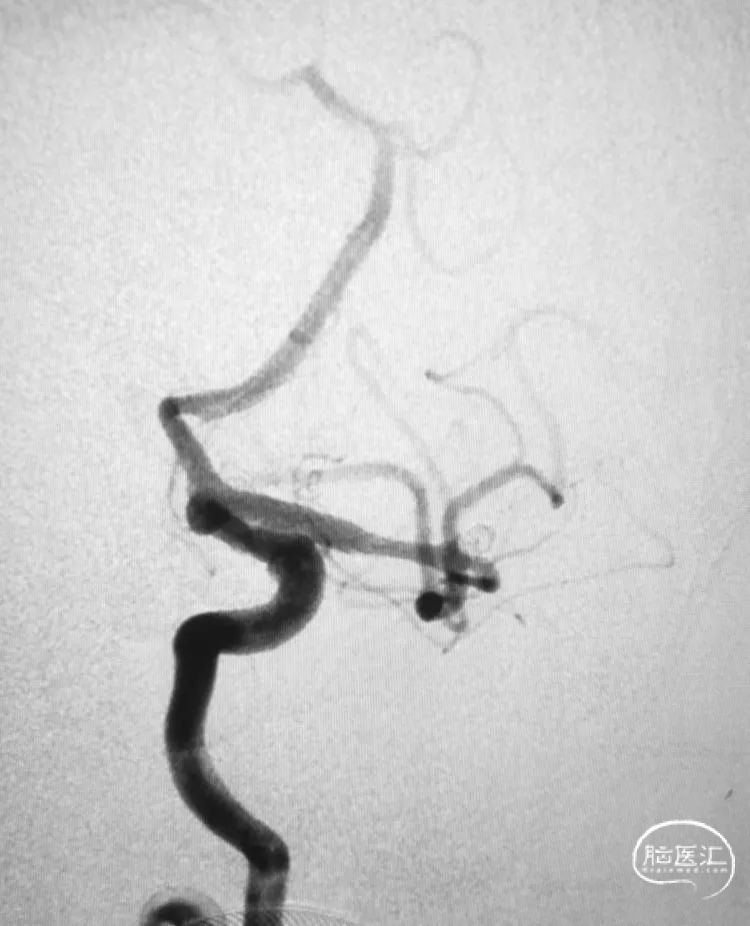

患者男性,75岁,发现大脑中动脉分叉部未破裂动脉瘤,瘤体不规则,有子囊,患者及家属治疗意愿强烈。

术前影像

多角度显示动脉瘤,中动脉分三干,瘤体和上干关系密切,宽颈,准备支架!Atlas非常适合这样的血管。